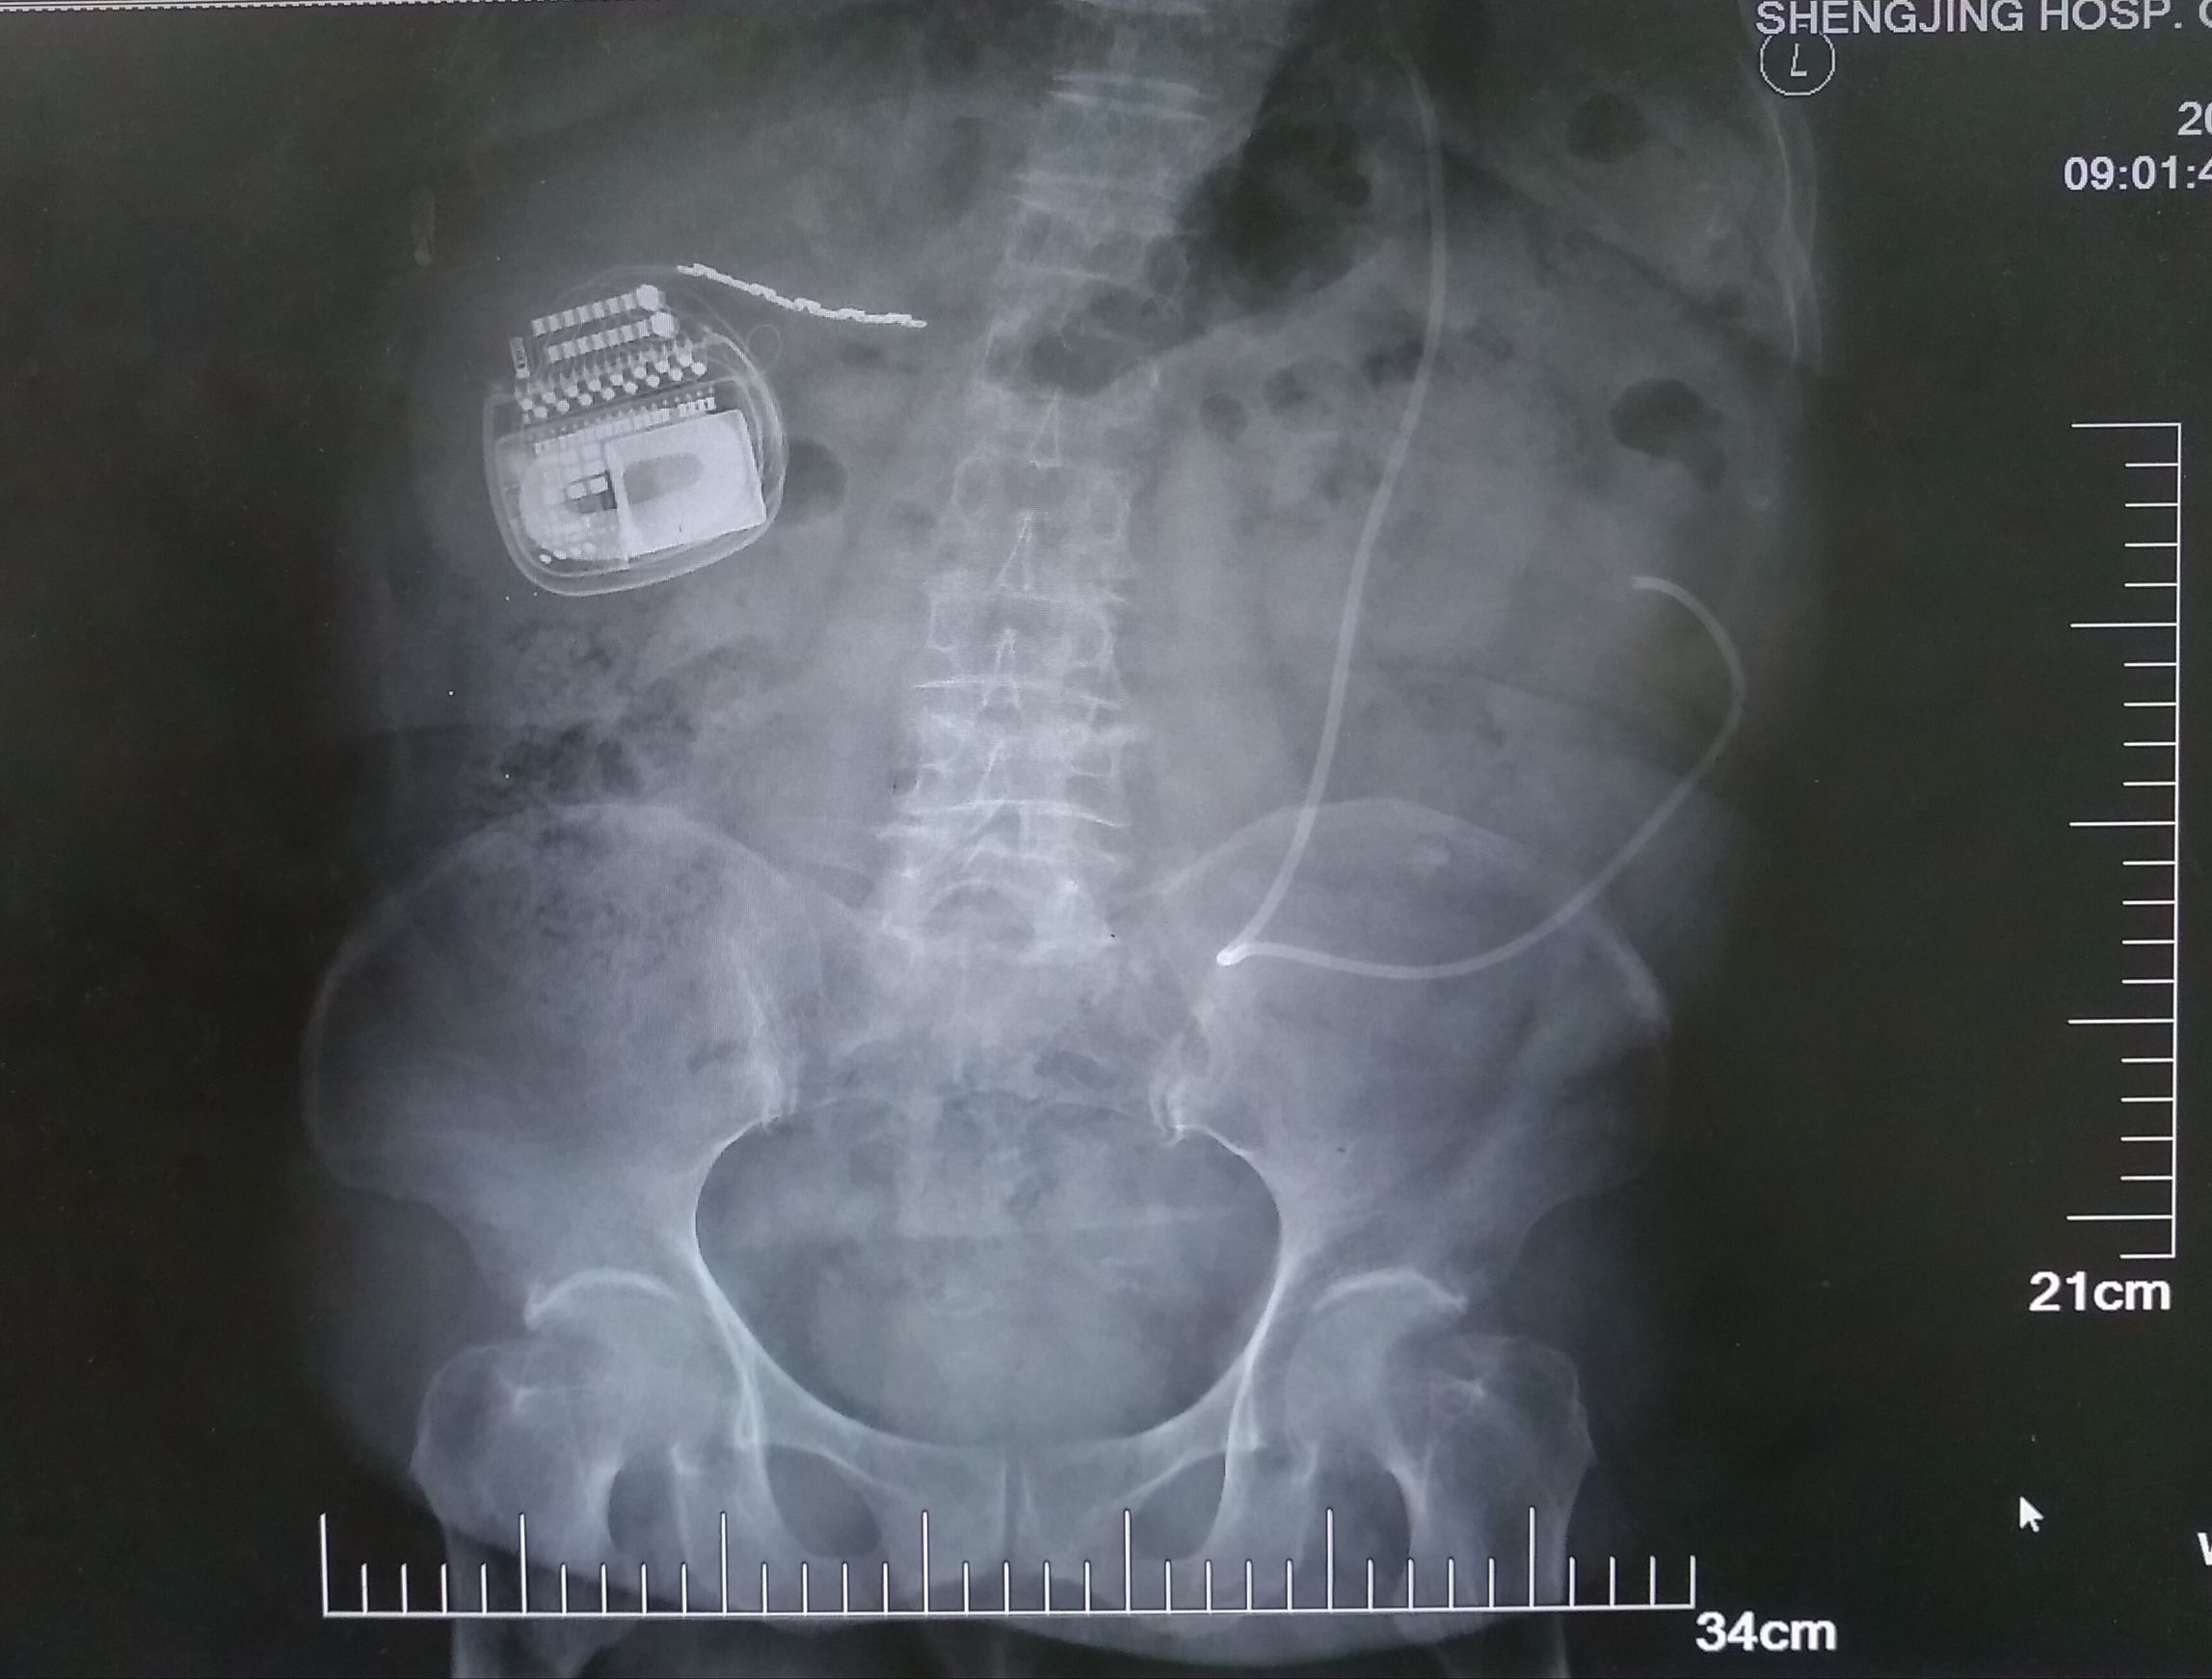

首先,鲍民副主任为高女士做了一期电极植入手术,在疼痛区域中心植入了一枚宽大的外科电极。手术过后,体内的电极通过延长导线和体外的临时刺激器连接上了。在开机的那一刹那,困扰高女士好几年的疼痛一下子就止住了。再也没有疼痛的袭扰,取代的是一丝丝电流的酥麻感,疲惫的高女士很快就进入了梦乡。 经过了七天的视察,在确认疗效满意后,鲍民副主任为高女士行二期手术,植入了最新的可充电式、可感知体位变化的Restore Sensor®刺激器(图)。术后高女士疼痛缓解,可平卧,睡眠质量得到很大改善。

图 二期植入可充电刺激器及电极位置